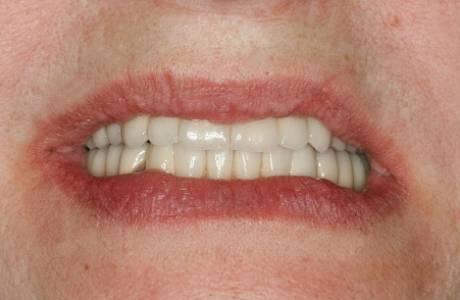

До лечения

Пациентка обратилась к врачу с полным отсутствием зубов.

После лечения

Были изготовлены и зафиксированы металлокерамические зубные мостовидные протезы на обе челюсти на имплантах. Пациентка очень довольна и красиво улыбается.